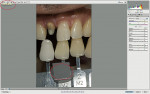

The next step is to determine the level of chroma, of which there are three in most of the M shades. They are labeled as 1, 2, and 3 (Figure 12). Again, it is best accomplished by a process of elimination, recording the closest match or noting if it is between two chroma levels. The chroma levels are all exactly equidistant from each other within the color space. With the Linearguide, all of the different chromas of all three hues are in a special holder (Figure 13). Using this system makes it easier to see if the chroma is an in-between level. The author passes the chroma guide of the closest value in the same plane as the natural teeth, then photographs the two closest chromas (Figure 14).

The last step is to choose the specific hue. If the value and chroma are matched, experience has shown that an observer would not notice a shade mismatch in hue as long as the hue was within in the natural tooth range, but is noteworthy to evaluate if there is a reddish, orangish, or yellowish hue to the teeth. There are three specific hues: the middle hue (orangish), which corresponds to the middle range of natural teeth, a yellower hue, and a redder hue equidistant in color space from the middle hue. The author first evaluates the M hue of the closest value match relative to the tooth (Figure 14), and decides whether it matches or if it is redder or yellower, and then records the chosen hue. The final determination for the hue will be determined from the photography and computer analysis described in the next sections. Specific characteristics (ie, crack lines or decalcifications) can be recorded with high-quality photography.